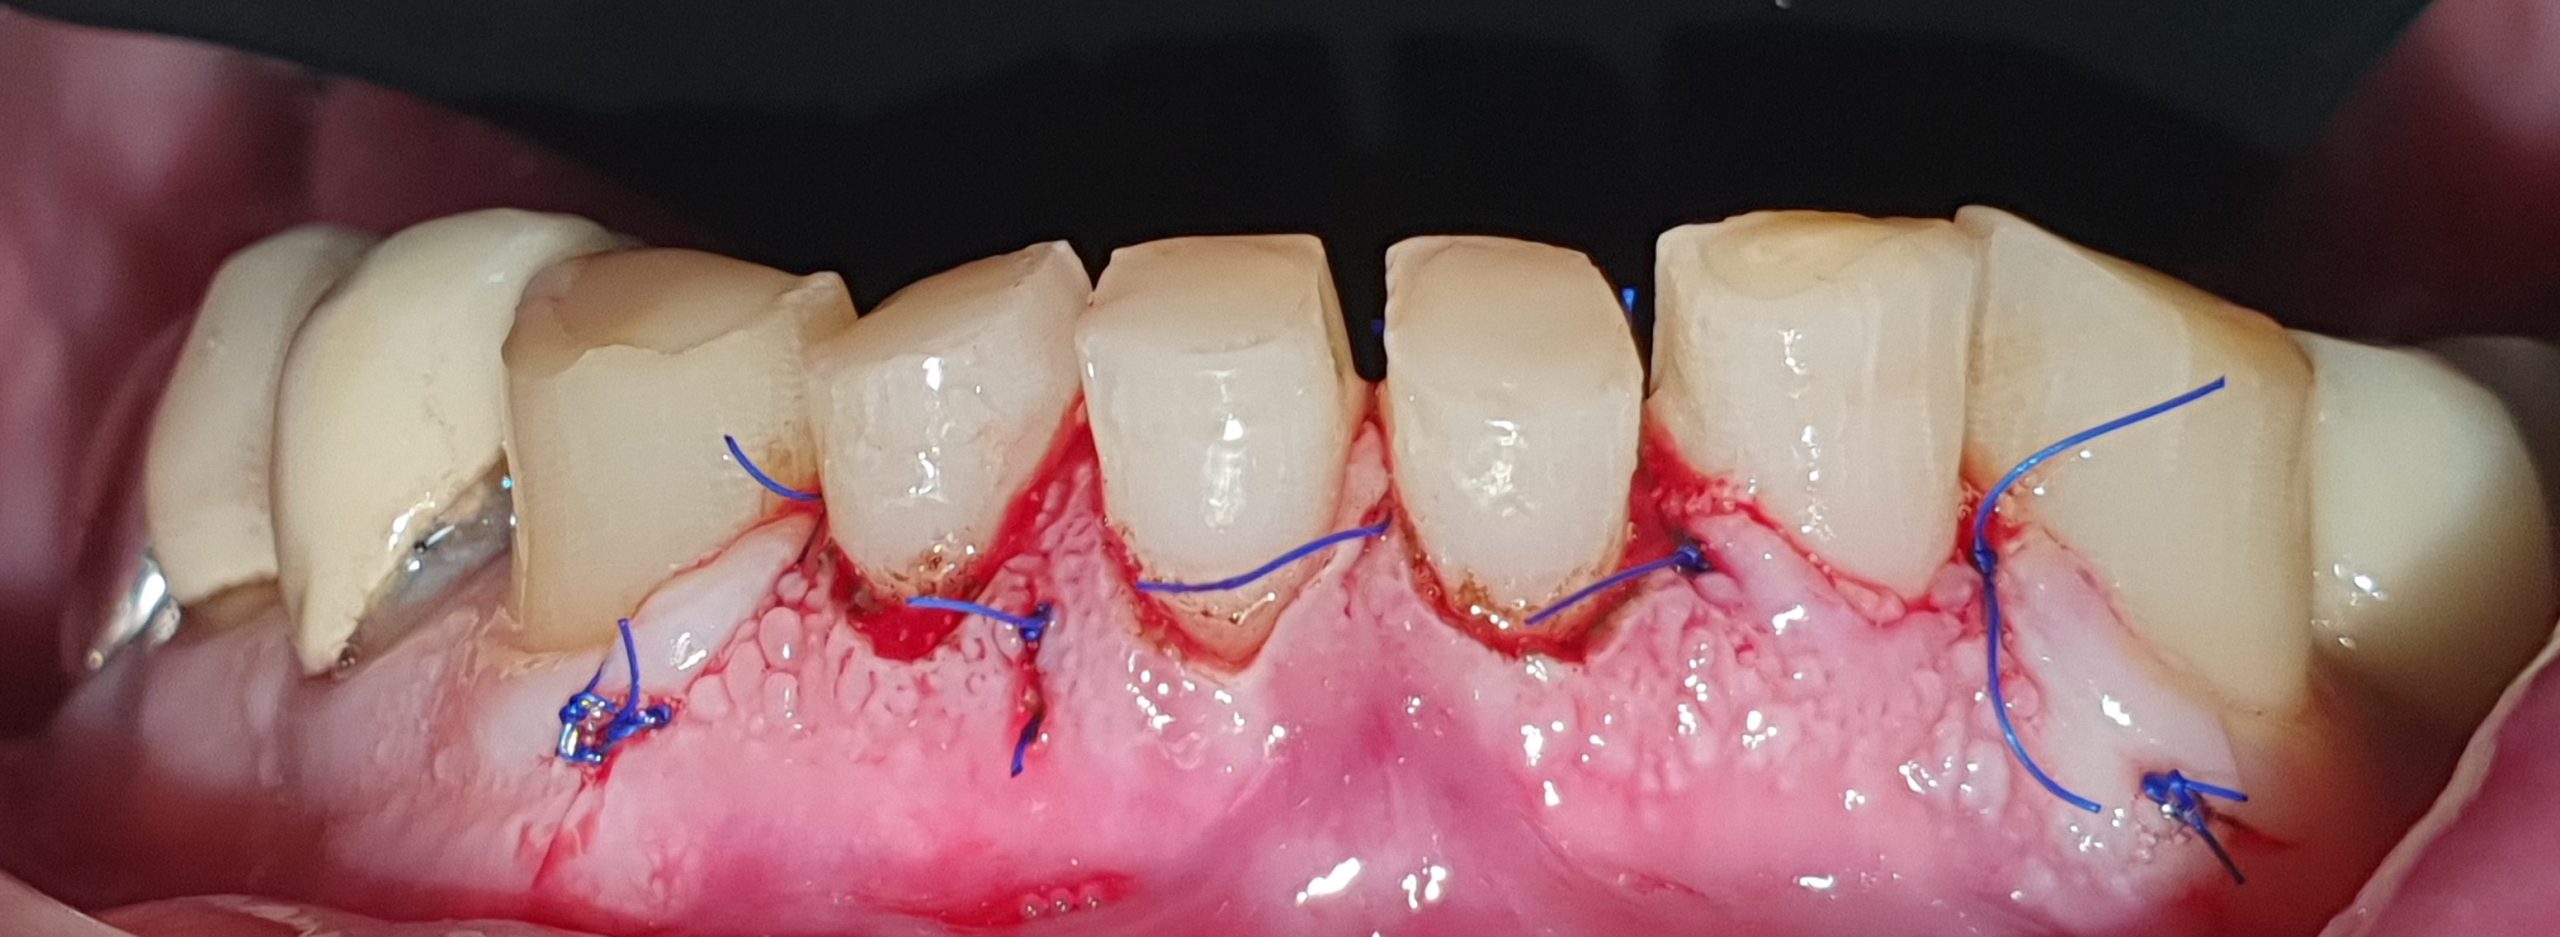

- Giai đoạn 2: phẫu thuật làm dài thân răng cửa dưới (33-43)

Giai đoạn 2: phẫu thuật làm dài thân răng cửa dưới (33-43)

Giai đoạn 3: mặt dán sứ veneer 6 răng cửa hàm dưới

Răng hàm dưới sau khi cắt nướu và gắn veneer